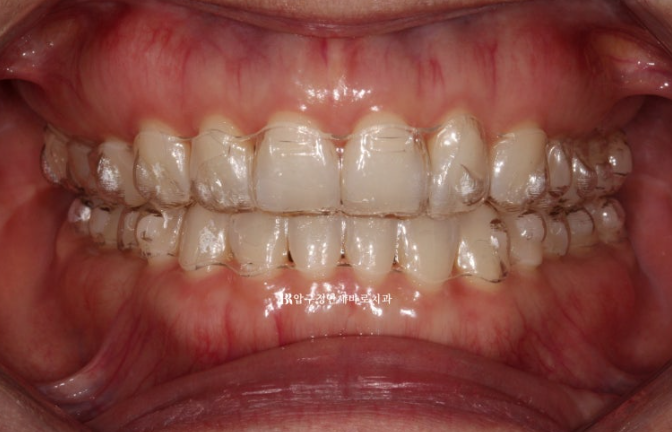

23년 7월부터 23년 12월까지 약 5개월에 걸쳐서 1차 세트 장치 14개를 다 착용한 후 모습입니다.

23.12

가위교합과 벌어졌던 공간은 이미 해결이 되었습니다.

중심선도 잘 맞습니다.

블랙 트라이앵글과 치아 사이 미세공간 마무리를 위해 추가적인 제작에 들어갑니다.

가위교합은 1차 세트에서 완전히 개선이 되었기에 미니스크류는 추가장치 제작을 하기로 한 날 제거했습니다.